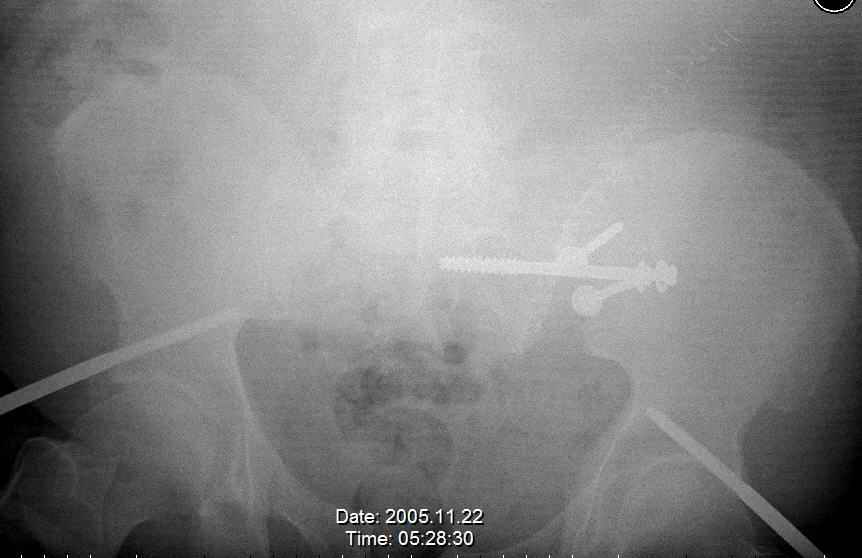

Hello gentlemen- Case is 52 YO male, fell out of treestand while deerhunting. He is 6 ft, approx. 260-275 lbs. Was hemodynamic unstable at local ER, sent to our Trauma center where circumferential pelvic binder placed and pt. stabilized with fluid, blood, and rewarming. Angiography not performed. An extraperitoneal bladder disruption was found, uro elected to treat non-operatively. Initial xray (not shown) demonstrated 5-7 cm wide at symphysis and SI joint. The first image attached is of CT once binder is in place. On post trauma day 5 the pt was taken to OR for ORIF of his iliac wing fracture and SI dislocation. The swelling/3rd spacing of fluid in the area of symphysis was profound, but quite acceptable posteriorly. Patient was prone for procedure, as I thought too difficult to fix the wing in lateral position. Of course the repair of wing was easy, but reduction of SI very demanding. The Floro images document the residual lack of reduction. That was the closest I could get it using 6mm joystick in wing, and clamp on sacrum and clamp through notch. The fixation was (initially) rigid. Anterior ex fix with supra-acetabular pins was placed due to condition of soft tissues, massive "beer-belly" overhanging the crest. Post trauma day ten patient's xray shows failure of posterior construct. Plan was to perform revision orif once soft tissues resolve considerably for full anrterior fixation and posterior fixation. However, while Im away for holiday (on Post trauma day 15), pt is developing septic clinical appearance, and trauma suspects pelvic abcess near symphysis and performs I and D - finds nothing but no primary closure performed. Posterior tissues/incision continue to look healthy. Now is post trauma day 17, pt is still tubed/on dopamine/and wbc still elevated, anterior incision still packed open. Clearly must get to bottom of possible sepsis, but then what? Thanks for you time - sorry for such lengthy clinical description. Thomas Schaller Kalamazoo, Michigan

Request for more images.. Axial and coronal recon (pt in binder.)